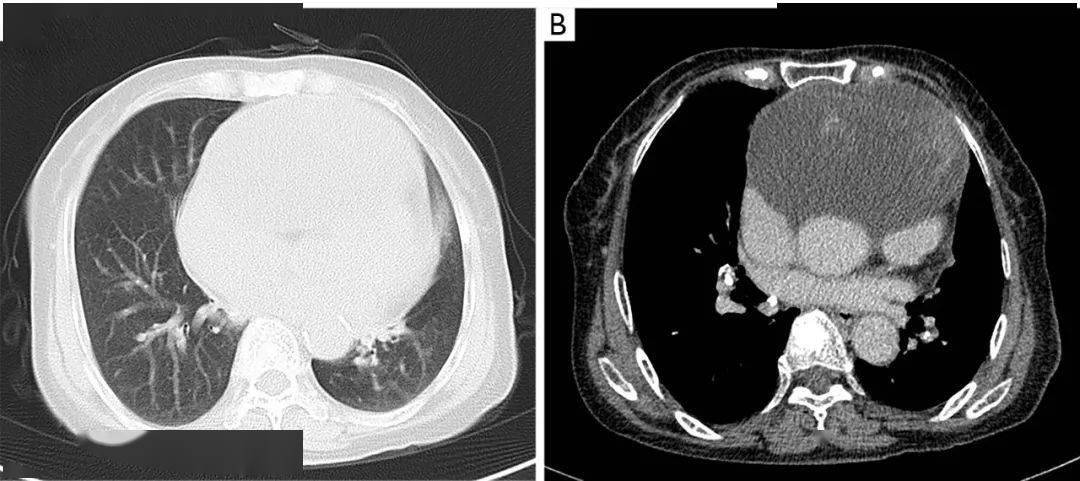

一例通过纵隔肿瘤切除诊断和治疗的心包间皮瘤病例|imdt 专栏_患者